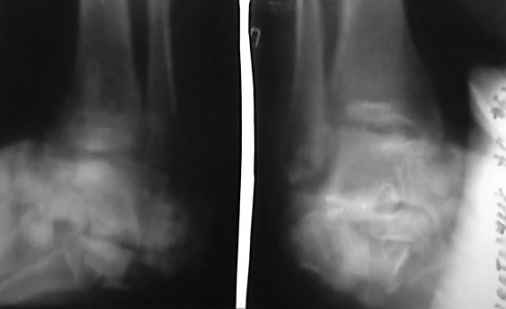

Отправляю снимки(свежие)и фото стоп.